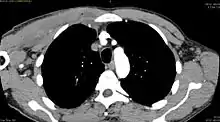

| Diagnostic method | Diagnostic method used for PM includes ultrasound, CT scan and MRI. Ultrasound can be helpful in showing muscular heterogeneity or a purulent collection but it is not useful during the first stage of the disease. CT scan can confirm the diagnosis before abscesses occur with enlargement of the involved muscles and hypodensity when abscess is present, terogenous attenuation and fluid collection with rim enhancement can be found. MRI is useful to assess PM and determine its localization and extension |